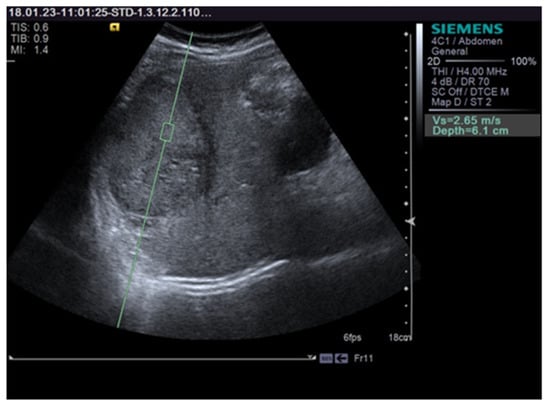

The VTQ results were expressed in m/s as the mean value of the 10 measurements. We assessed the intra-observer reproducibility and compared the first 5 and the last 5 EM. The ratio of VTQ measurements of each FLL vs. the surrounding liver parenchyma was also calculated. Figure 1 shows a VTQ measurement in an HCC nodule.

Figure 1. Shows a VTQ (Virtual Touch Quantification) measurement in an hepatocellular carcinoma (HCC) nodule.